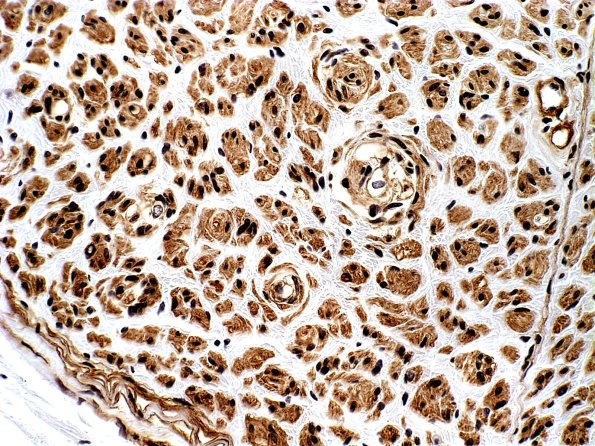

Washington University Experience | PERIPHERAL NEUROPATHY | 20 PSEUDO-ONION BULBS | 2B4 Pseudo-Onion Bulb (Case 2) Coll IV

Higher magnification images of image #2B1. The immunostain for collagen IV shows a general increase in the amount of basal lamina containing processes composing the POB structures. (Collagen IV IHC)